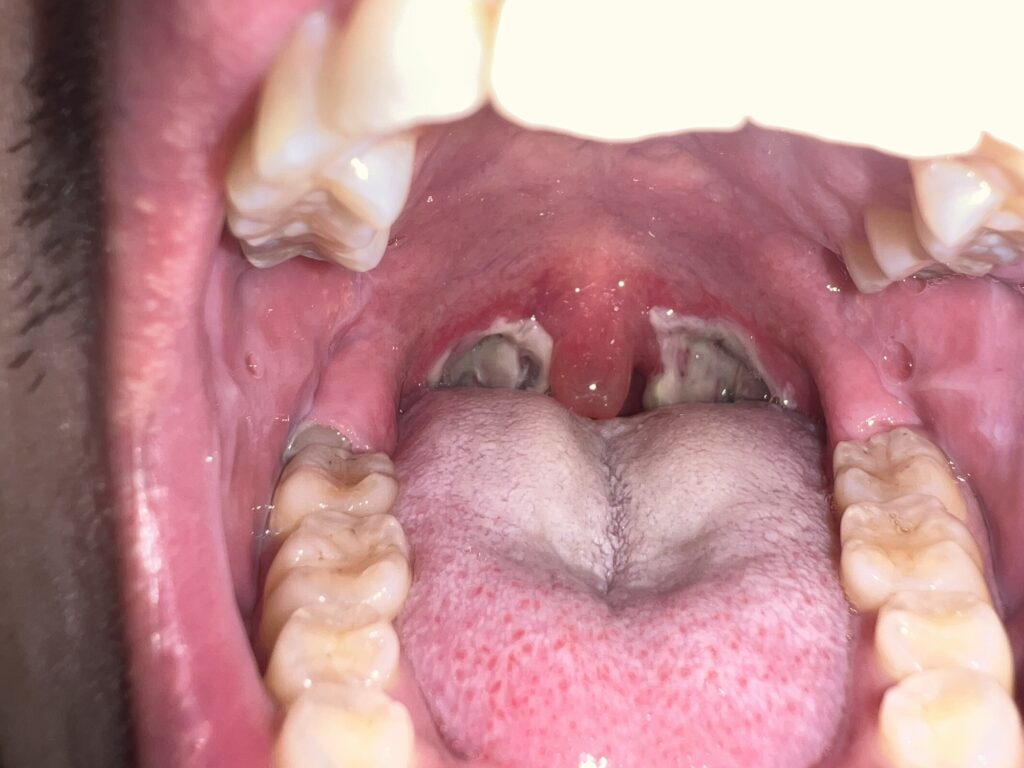

11月21日

もう僕的にはグロさしかないんですけども。早く完治してくれ〜。気持ち11月中にはって思いますけど、無理そうですね。

なにか黄色くなってますね。治ってきてる証拠なのでしょうか?早く普通食が食べたいです…